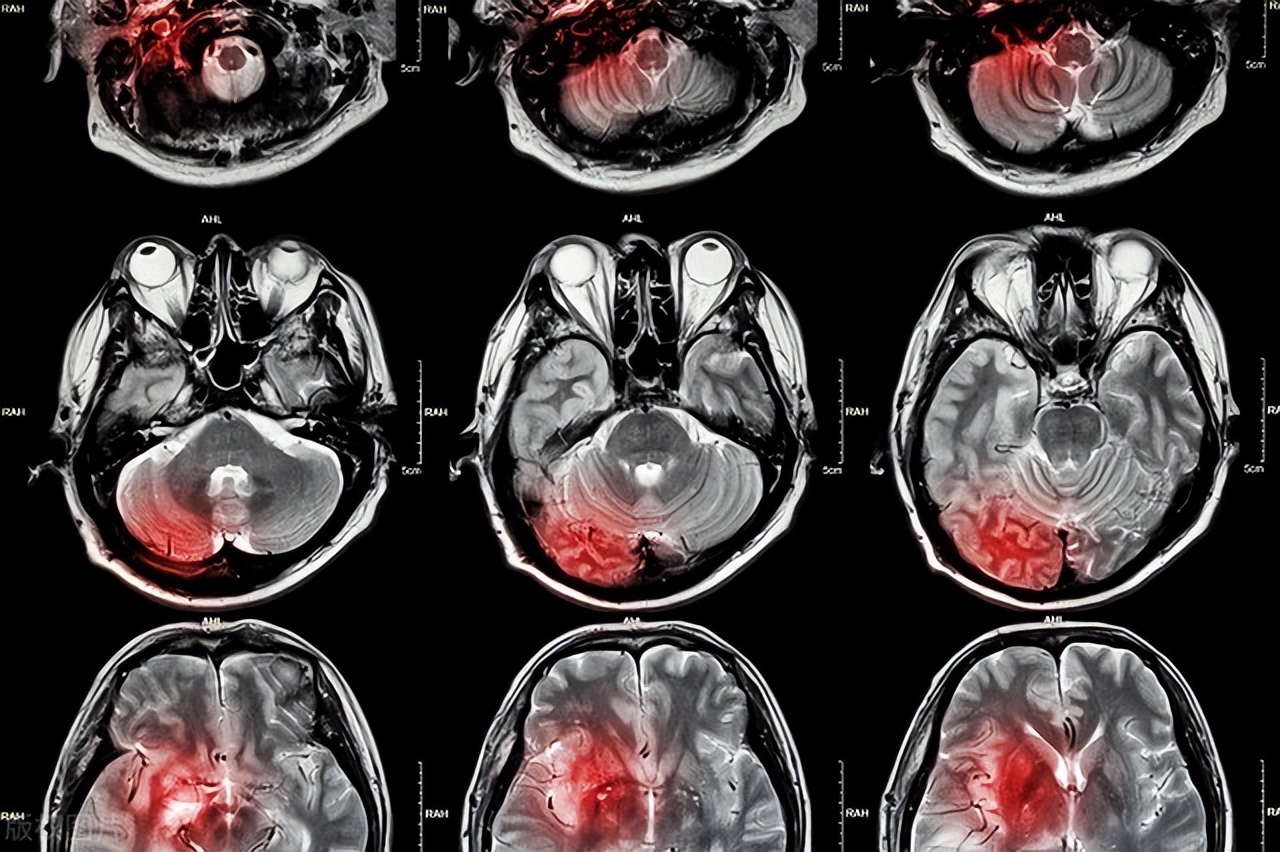

●脑梗死产生的病因是什么呢?是由于脑部的部分区域的动脉血流状态出现异常,造成供血能力不足的脑部区域出现缺氧、缺陷的现象,进而会随之出现脑组织软化、坏死等症状,在临床上患者出现失语、偏瘫等疾病体征。有相关的研究发现,在度过发病的24-48小时之后,运用脑部CT的手段可以观察到患病区域会出现低密度灶。另外,通过对脑MRI的检查可以及时的发现脑梗。脑梗死的临床表现多为头晕、昏迷、失语、恶心等,这些病症伴随着并发症而产生,诸如消化道出血、脑血管病后抑郁症、肺部感染、焦虑等。